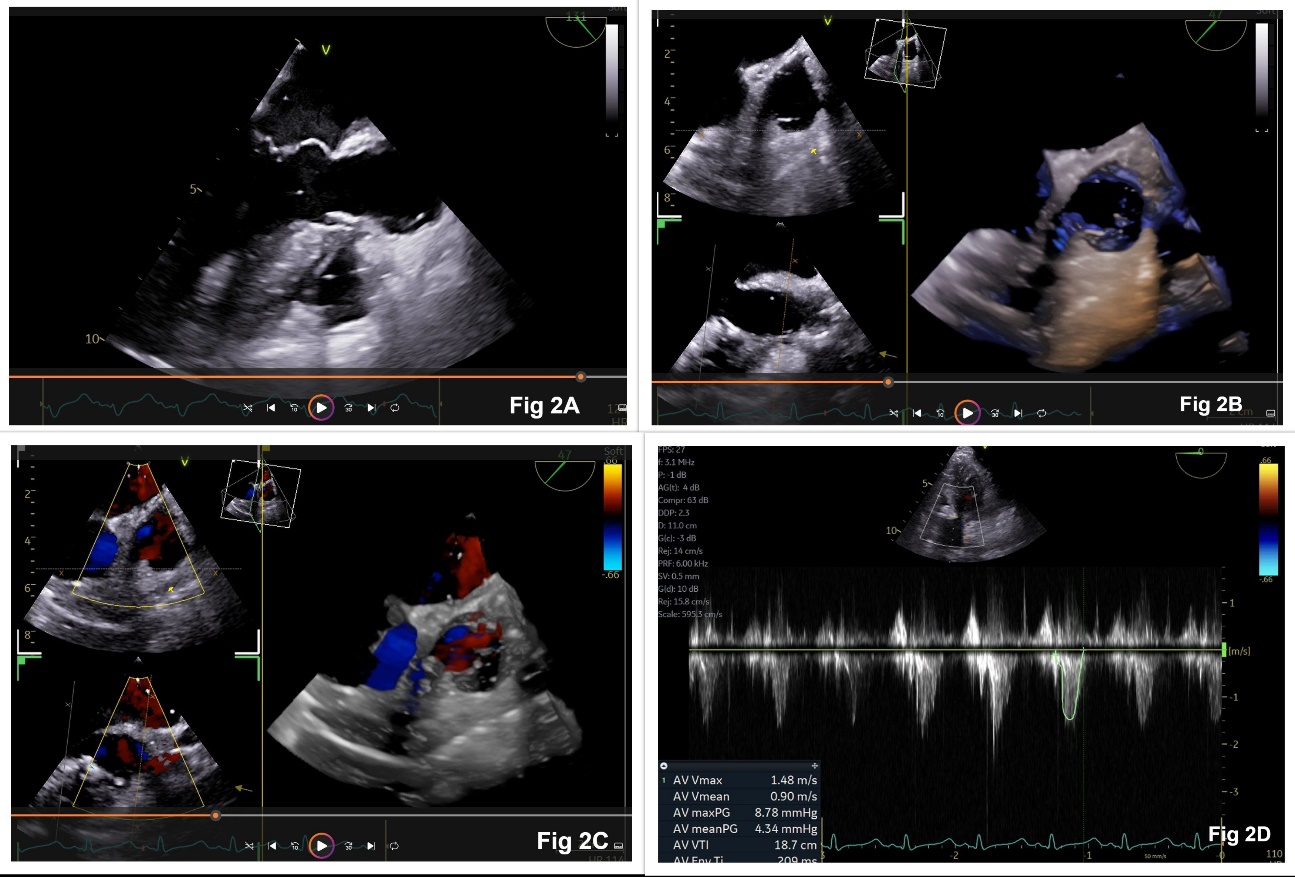

The surgical plan was the extrusion of the VSD occluder device and closure of the VSD using cardiopulmonary bypass (CPB). Informed consent was obtained. Under standard cardiac monitoring, general anesthesia was induced and a transesophageal echocardiography (TEE) probe (6 VT-D transducer, Vivid E95 GE) was inserted. Intraoperative TEE confirmed the preoperative echocardiographic findings and showed significant narrowing of the LVOT (Figure 1A-1D). LVOT gradient measured during intraoperative TEE was 77/37 mmHg (Figure 1E). The surgical procedure consisted of a midline sternotomy, systemic heparinization, bicaval and aortic cannulation, and institution of CPB. During surgery, the VSD occluder device was found to be tightly adherent to the LVOT and the interventricular septum. A forceful extrusion of the device could have led to damage to the aortic valve, the LVOT, the interventricular septum, and other neighboring structures. It could even have led to the formation of an iatrogenic VSD. Therefore, the surgeons decided to remove the left disk of the VSD occluder device by performing its debulking with Rongeur forceps and reassess the relief of LVOT obstruction. The subaortic membrane was resected. After coming off CPB, TEE showed LVOT pressure gradients of 8/4 mmHg (peak/mean), trace aortic regurgitation, a VSD device in situ, and no residual VSD shunt (Figure 2A-2D). The remaining surgical procedure and the postoperative course were unremarkable.

Figure 2: Postoperative transesophageal echocardiographic images showing wide open left ventricular outflow tract (LVOT, Figure 2A), absence of occluder device in LVOT (Figure 2B), no turbulence in LVOT (Figure 2C), and low pressure gradient across LVOT (Figure 2D)